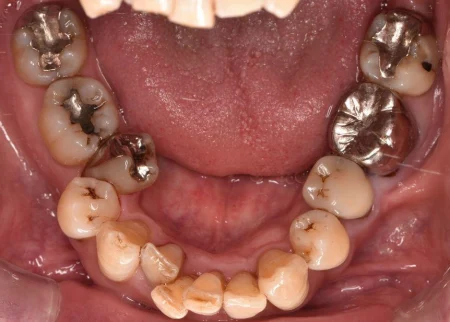

治療前

| カウンセリング・診断結果 | 拝見すると、お口全体の歯の表面に重度の着色が見られました。 患者様は「日ごろからよくコーヒーを飲む」とのことで、これが着色の原因と考えられました。 さらに、レントゲン写真や歯周検査の結果から、歯肉に炎症が起こり歯を支える骨が次第に溶けていく「歯周病」の進行も認められました。 |

| 行ったご提案・治療内容 | 歯周病を放置したまま詰め物をやり直すと、歯と詰め物の間に隙間が生じやすく、その隙間から虫歯になったり歯周病がさらに悪化したりする場合があります。 また、着色があると歯の表面のざらつきが原因で、食べ物の残りカスに細菌が繁殖した「プラーク」が付着しやすくなります。 そのため、詰め物をやり直す前に歯周病の治療と着色除去を行い、歯と歯肉の状態を改善する必要があることを丁寧にご説明し、ご理解とご了承を得ました。 歯周病治療は、歯肉の上や歯肉の中にあった硬い細菌の塊「歯石」を除去しました。 また、専用機械による歯の表面のブラッシングや、ジェット水流と専用パウダーで汚れを除去する「エアフロー」で着色を取り除きました。 着色の度合いが強かったため、歯周病治療と着色除去を並行して4回に分けて実施しました。 |